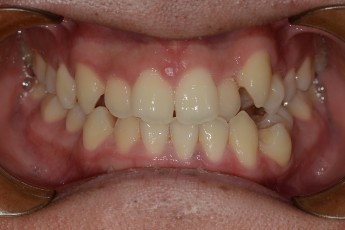

BEFORE & AFTER

- 덧니교정